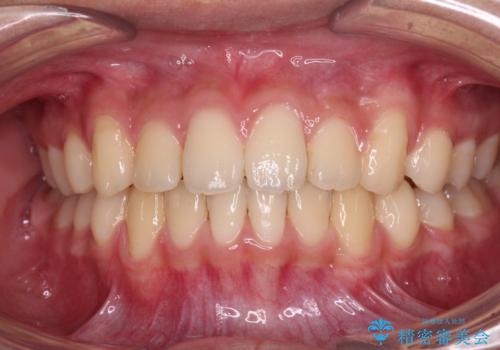

前歯の隙間とデコボコを改善 高校生のインビザライン治療

- 前歯のデコボコと隙間を気にして来院された高校生の患者様です。

下顎前歯が上顎前歯を突き上げるような咬み合わせとなっており、その影響で上顎正中に隙間ができている状態でした。

叢生の程度は軽度であり、本人もしっかりと使用する自信があるとのことだったので、インビザラインによる矯正治療を行うこととしました。

突き上げによる隙間を予防する為に、深い咬み合わせを改善するような治療計画としました。咬み合わせを改善させることはできましたが、隙間は後戻りしやすいので、通常の下顎前歯のみではなく、上顎前歯2本もワイヤーで保定を行いました。

高校生ということで、非常に短期間で治療を終えることができました。